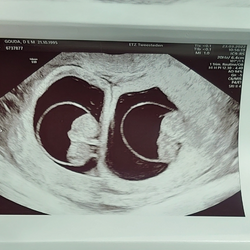

Ik ben zwanger van een tweeling. (Gezien bij 6,5 week)

Ze zitten in 2 plasenta's met een dik tussenschot.

Helaas was er op die echo nog geen hartactie te zien, maar wel twee even grote vruchtzakjes met dooiers.

Vandaag eerste echo gehad. Ben 6 weken. Tot mijn verbazing zijn het 2 vruchtzakjes. Bij 1tje het hartje zien kloppen. Bij de andere nog niet. Maandag mag ik terug 馃グ

Hier ook een tweeling, dacht 8 weken te zijn maar is 6+5 nog super klein, maar beide hartjes waren al kloppend te zien

Ik ben net weer in het ziekenhuis geweest voor de controle bij de gynaecoloog. Afgelopen maandag heb ik ze dan ook gezien omdat er toen het gesprek hadden over de nipt test etc weer wat minder leuk dat gesprek.... Vandaag was het wel heel leuk! Ze waren allebei flink gegroeid en dat in nog geen week. Ze zitten allebei apart hebben allebei een eigen placenta en eigen vruchtzak met een dik tussenschot beter kon het niet zei ze. Ze zag dat de nek plooien mooi dun waren dus ze zei al dat we ons nu nergens druk over hoeven te maken. Ze hebben lekker veel vruchtwater en de navelstreng van beiden kon ze al goed zien. Alle handjes voetjes armpjes en beetjes waren goed te zien! Al 2 echte kleine mini mensjes 馃槏馃グ馃グ ik ben vandaag 11,1. Ze vertelde ook al dat ze bij onze geplande keizersnede aanwezig is mits ze zich zelf gaan aankondigen dan is dat natuurlijk de vraag. Hele lieve gynaecoloog